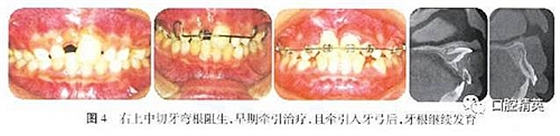

上頜中切牙的彎根阻生,其臨床治療開始時機尚無定論。從患兒心理健康及患兒家長的臨床主訴方面考慮,筆者提倡早期正畸牽引治療(圖4)。

作者認(rèn)為,在生理性矯治力的作用下,上頜中切牙的阻生彎根可在正畸牽引力的作用下,改變彎曲角度,并沿牽引力的方向繼續(xù)發(fā)育,正畸早期牽引可以改善牙根的進一步彎曲,促進彎根牙的牙根發(fā)育,所以牽引彎根牙的治療時機可以提前,牙根發(fā)育開始階段進行的正畸牽引不一定產(chǎn)生不良的治療后果。